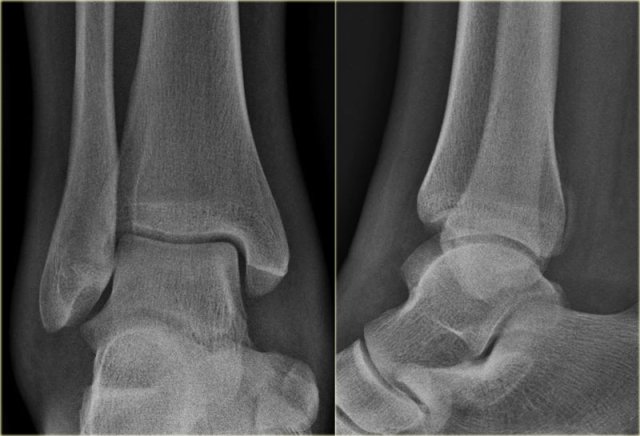

Study the images and then scroll to the next images.

The fracture through the epiphysis can be easily missed (blue arrow).

The fracture through the growth plate is only seen on CT.

This is also a Salter-Harris type III fracture.

Notice that there is also a Tillaux fracture.

We will discuss these fractures in a moment.